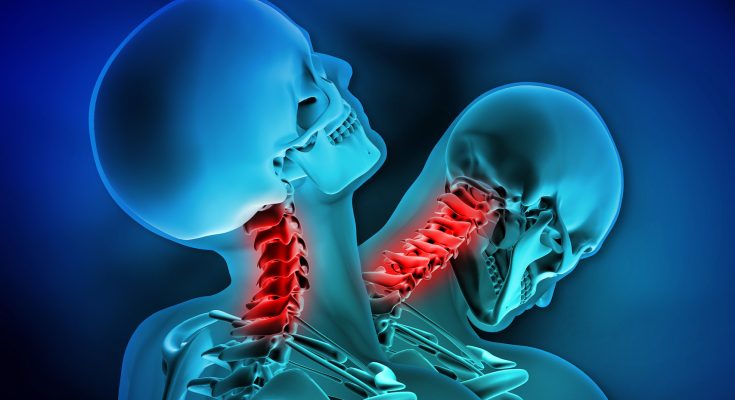

In September 2022, the Journal of Orthopaedic Case Reports published a troubling case involving an 18‑year‑old male worker in India who sustained a severe cervical spine injury after a heavy metallic object fell directly on the front of his head while he was at work. This rare and catastrophic injury led to a retropulsion fracture of the C5 vertebral body, associated with a C6 fracture, and despite emergency care, the victim died two days later. This is the first recorded case of such injury morphology that defies standard classification systems.

Once in the emergency department, the patient underwent non‑contrast computed tomography (NCCT) of the cervical spine. The images revealed:

- An isolated retropulsion of the C5 vertebral body into the spinal canal.

- Notably, no displacement of facet joints or pedicle fractures was seen.

- A concurrent fracture in the postero‑superior portion of the C6 vertebral body was also identified.

Such an axial flexion‑compression injury, where the vertebral body is compressed and displaced backward (akin to a “nutcracker” effect), is exceptionally rare and has not been categorized within common classification systems such as Allen & Ferguson, SLICS, or AO Spine ([turn0search3], [turn0search0]). This was the first documented instance of this specific fracture pattern in medical literature.

The subaxial cervical spine (C3–C7) is structurally mobile, responsible for most neck movement. When force is applied along the head-to-spine axis, vertebral bodies such as C5 can be crushed between adjacent vertebrae. In this case, the downward force created a “nutcracker-like” compression that fractured C5 and drove it backward into the spinal canal, while also creating a secondary fracture at the superior posterior corner of C6 ([turn0search0], [turn0search3]).